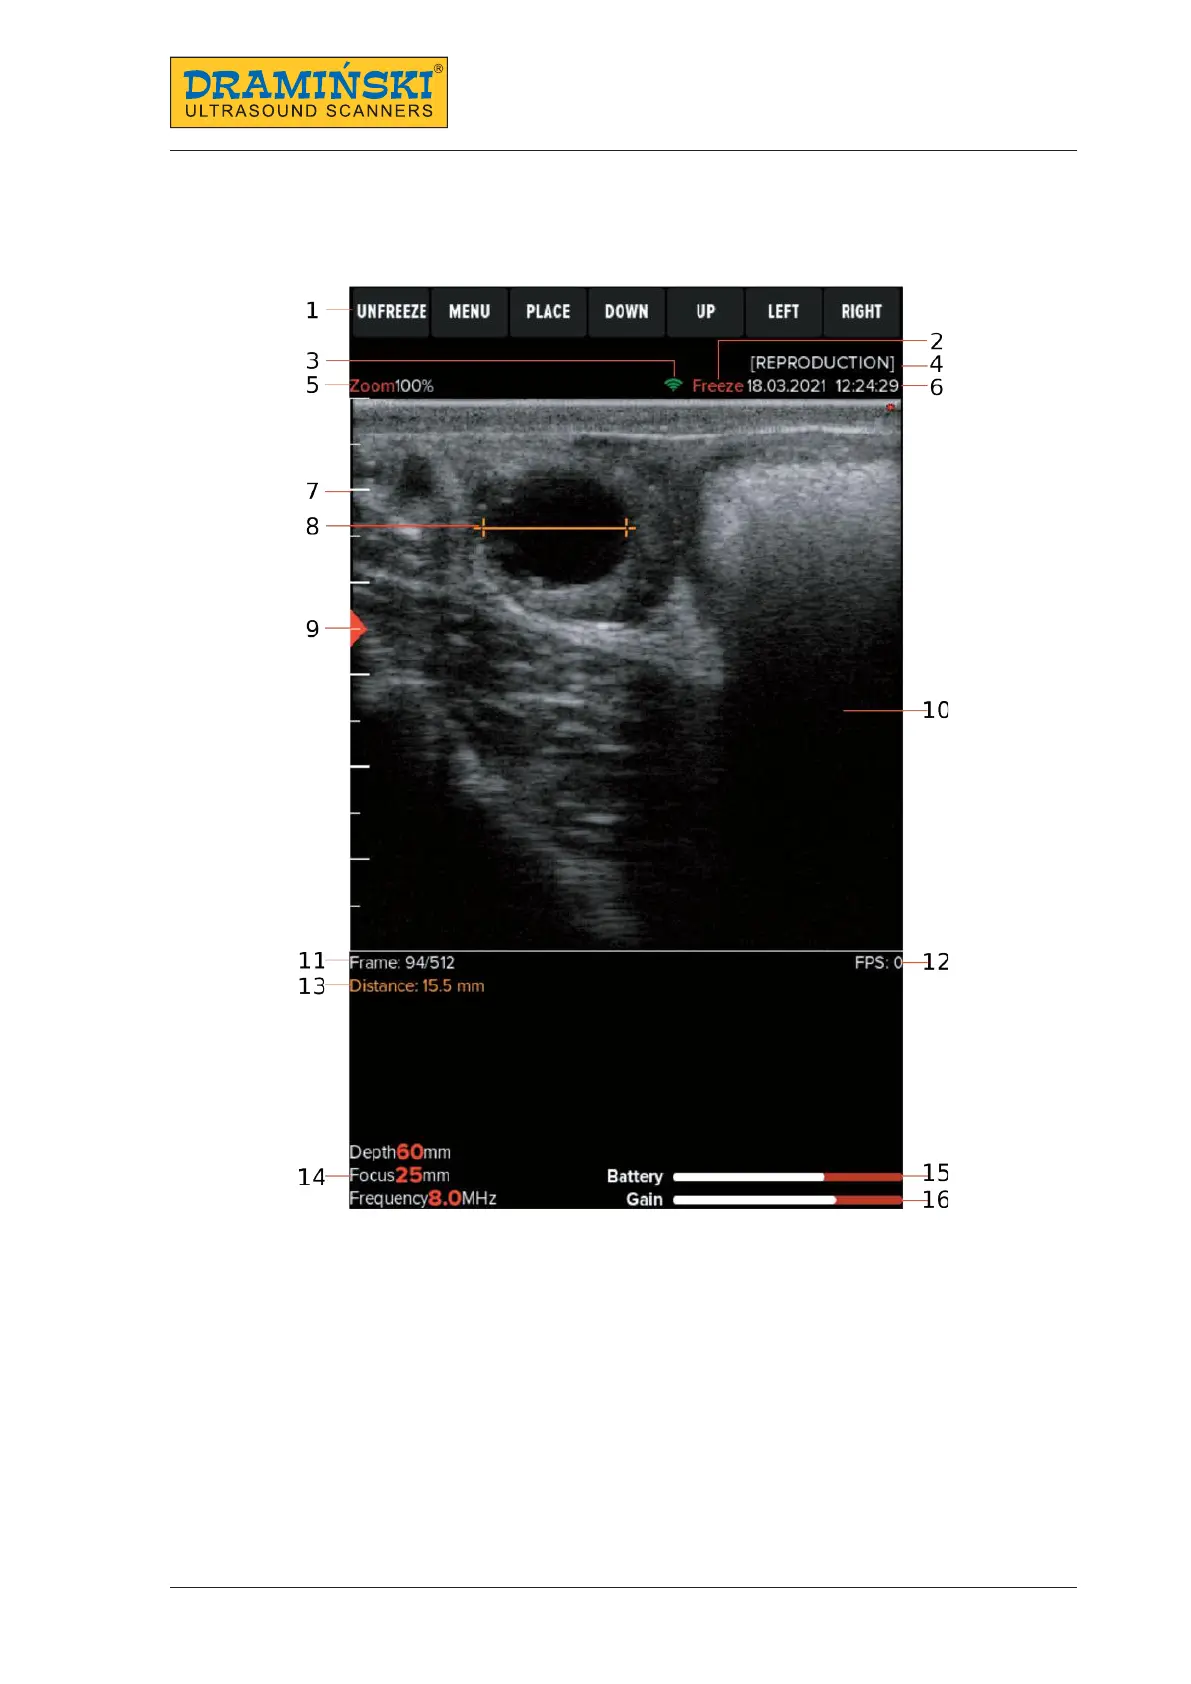

7. User control panel

7.1. User control panel’s structure

User control panel

1. Button functions

2. Information about freeze mode

3. Information about active WiFi connection

4. Set preset name (if turned on)

5. Zoom

6. Date and time

7. Centimetre scale

8. Distance measurement

9. Beam focusing level

10. Image sector